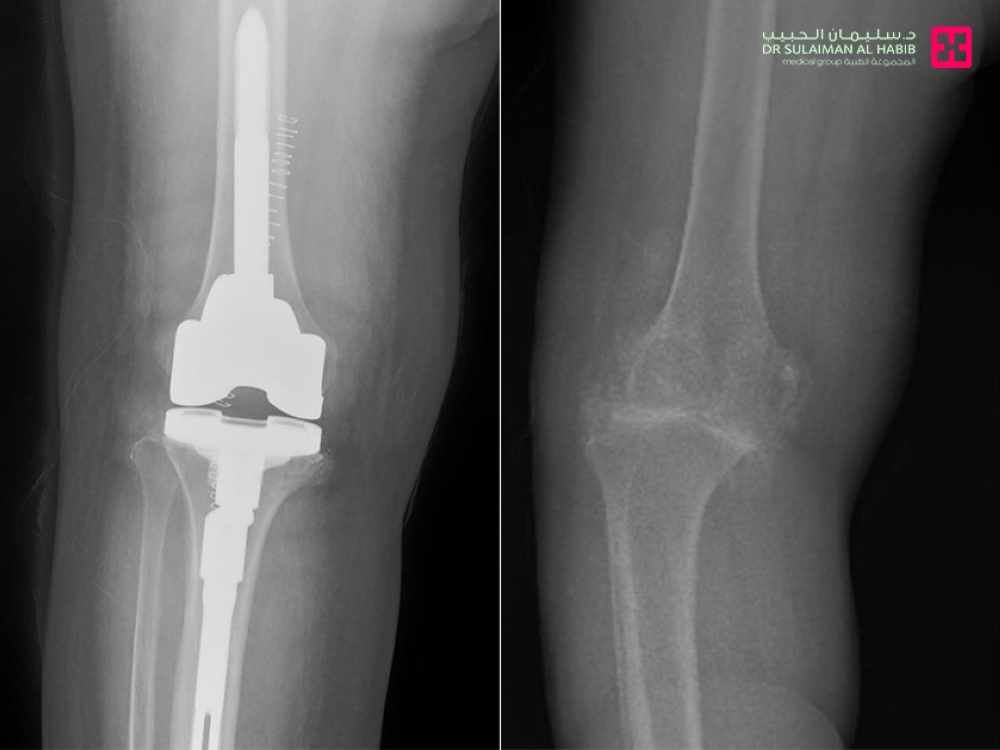

بفضل الله – أعاد مستشفى الدكتور سليمان الحبيب بالخبر، القدرة على الحركة لامرأة تبلغ من العمر “75” عاماً، بعد عملية استبدال مفصل ركبة متقدمة، وأنهى التدخل الطبي معاناة السيدة مع الكثير من الأعراض الحادة، التي أهمها عدم القدرة على المشي.

وقال د. حمد الشهراني استشاري جراحة العظام والمفاصل الصناعية، والطب الرياضي، رئيس الفريق الطبي المعالج، أن المراجعة جاءت إلى المستشفى على كرسي متحرك، مشتكية من عدم القدرة على المشي، وآلام حادة وتورم وتشوه في مفصل الركبتين، بالإضافة إلى تيبس وصعوبة في ثني الركبة، وخضعت لفحوصات طبية دقيقة، حيث أكدت صور الأشعة الطبية، وجود خشونة حادة بمفصل الركبة، مع تآكل بالعظم وارتخاء الغضاريف التي تحيط به وتحميه من الاحتكاك بشكل مباشر، وسبب كل ذلك في عدم قدرتها على الحركة وتقوساً بالركبة، وتمت مناقشة الحالة وفق معطيات التشخيص من قبل الفريق الطبي، ووضع خطة علاجية متكاملة، وأجريت لها عملية استبدال مفصل، في تدخل طبي استمر لنحو “90” دقيقة وقد تكللت ولله الحمد بالنجاح، وتم تحويلها مباشرة إلى جناح التنويم، حيث أمضت “4” أيام محاطة بالعناية الطبية الحثيثة، وبدأت في المشي على قدميها بعد العملية بساعات، وواصلت خلال تنويمها العلاج بالأدوية، بالإضافة إلى تنفيذها لبرنامج علاج طبيعي متكامل، وتحسنت حالتها الصحية باضطراد، إلى أن غادرت المستشفى وهي بصحة جيدة، حيث زال التقوس واستعاد الساق شكله الطبيعي، كما أنها تخلصت من الآلام وغيرها من الأعراض الحادة، التي كانت تنغص حياتها، إضافة إلى أنها استعادت قدرتها الكاملة على الحركة، حيث غادرت المستشفى إلى منزلها مشياً على قدميها وبحالة نفسية ممتازة.